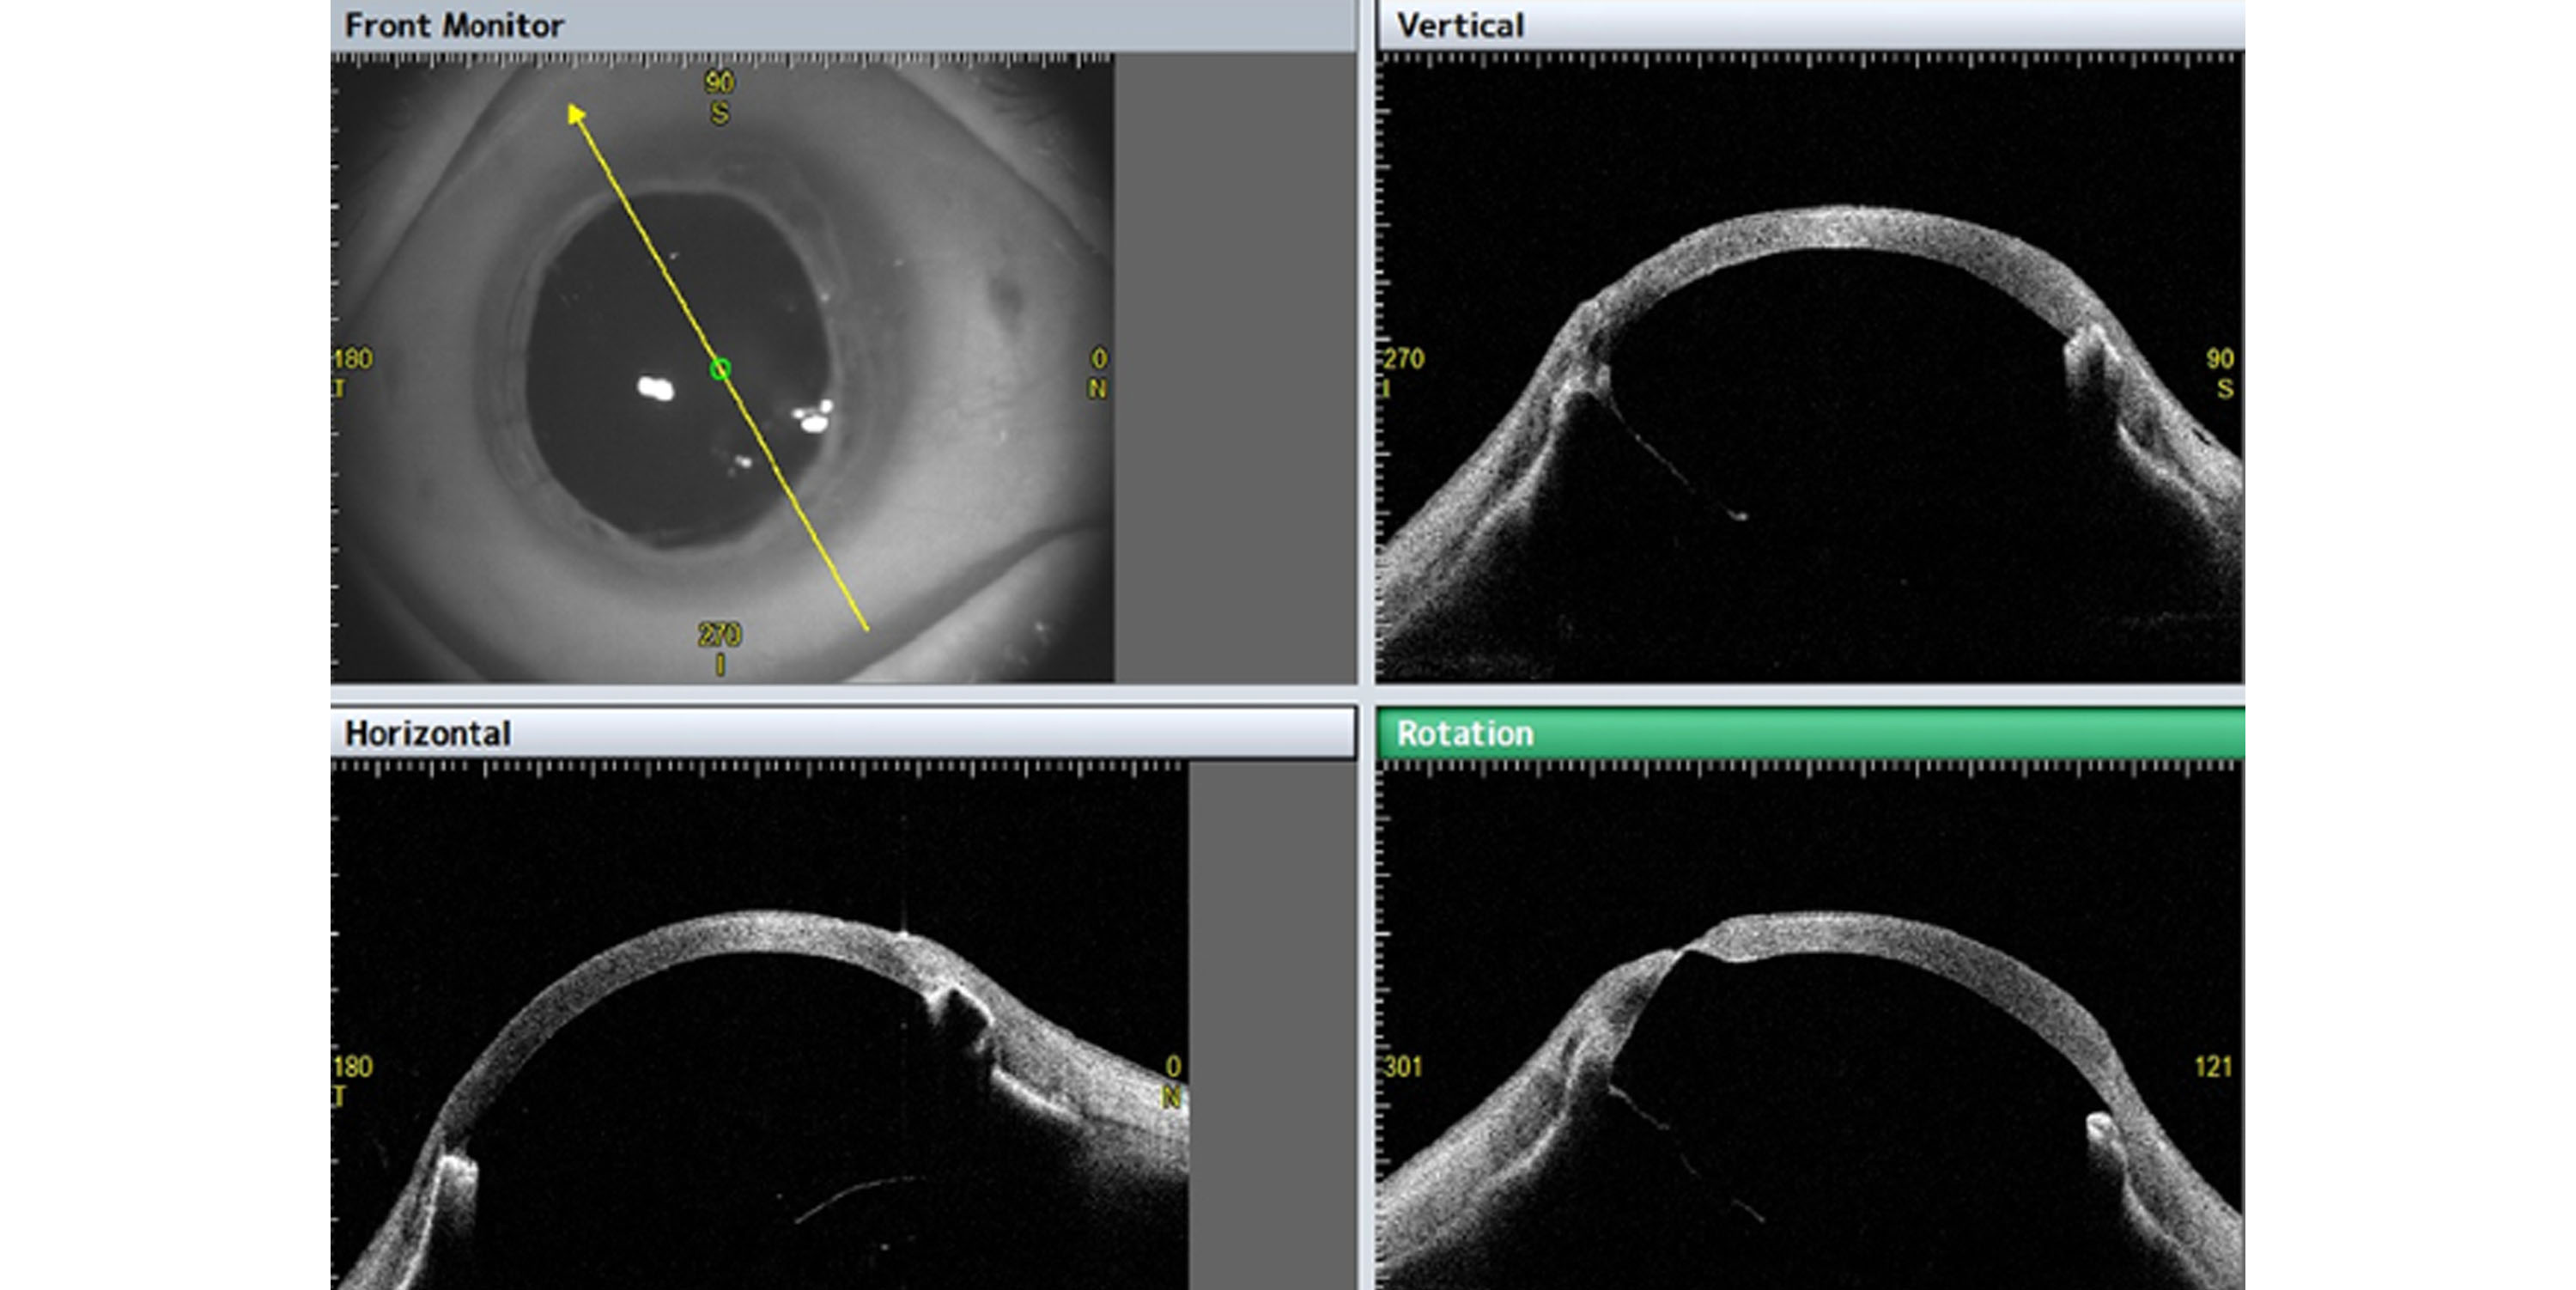

Conçu pour une analyse complète de la cornée et du segment antérieur, le système CASIA 2 de Tomey est doté d'un moteur OCT à source balayée haute vitesse qui délivre une imagerie rapide et haute résolution. Cela garantit une visualisation précise des structures oculaires, essentielle pour un diagnostic et une planification de traitement précis. Le CASIA 2 permet un examen détaillé de la topographie cornéenne, de la pachymétrie et des mesures de l'angle de la chambre antérieure, permettant aux cliniciens d'évaluer diverses conditions telles que le kératocône, le glaucome et les résultats post-chirurgicaux. Son logiciel intuitif comprend des modes d'analyse automatisés et personnalisables, améliorant l'efficacité et la fiabilité diagnostiques. Avec une vitesse de balayage avancée de 50 000 A-scans par seconde, le CASIA 2 réduit le temps d'attente des patients tout en maintenant une qualité d'image exceptionnelle. Le système présente également une large gamme de balayage, répondant facilement à divers besoins cliniques. De plus, le CASIA 2 prend en charge une intégration transparente avec les flux de travail cliniques existants grâce à sa compatibilité DICOM et son interface conviviale.